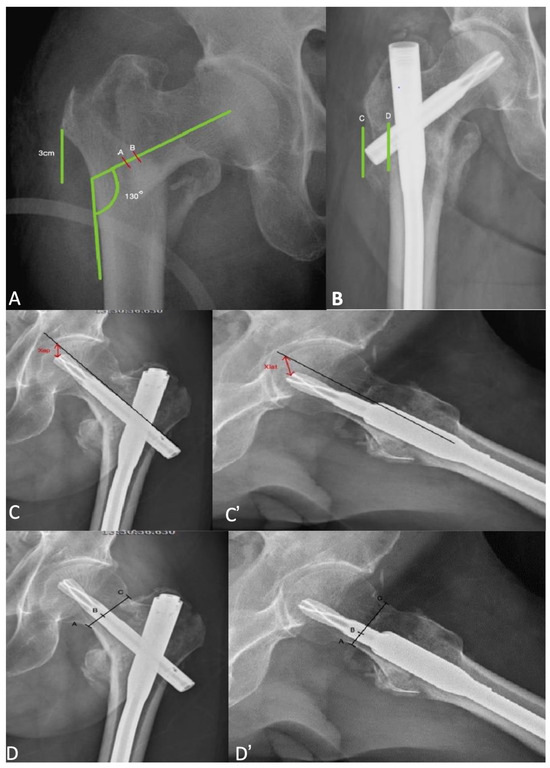

2.2. Data Collection and Assessments